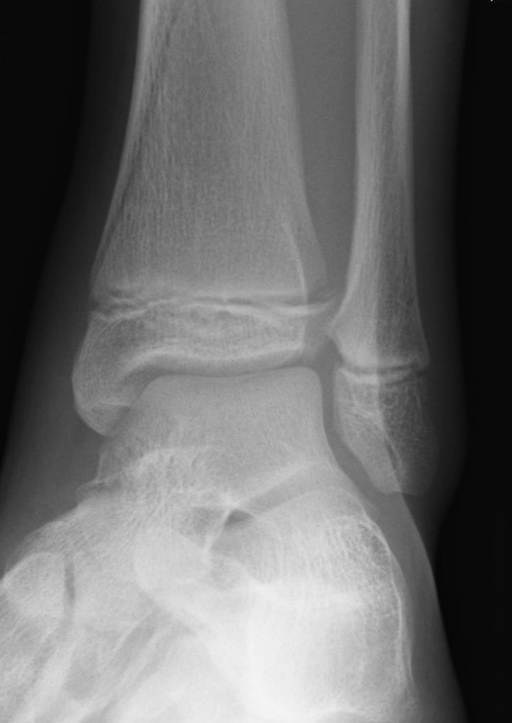

Fugengelenkfrakturen treten typischerweise vor dem 10. Lebensjahr auf, in einer Phase, in welcher die Wachstumsfugen noch weit offen sind. Dieser Frakturtyp betrifft fast ausschließlich den medialen Malleolus. Laterale Frakturen sind extrem selten, teilweise kommt es zu lateralen Bandverletzungen oder Fugenschaftfrakturen der distalen Fibula. Die Frakturlinie verläuft in einer Verlängerungslinie von der medialen Taluskante nach proximal. Häufig stellen sich Verletzungen des Innenknöchels im Röntgenbild schlechter dar, insbesondere wenn die Aufnahmen verdreht sind oder die Ebene der Fraktur bei geringer Dislokation verkippt zur Röntgenebene liegt. Besteht klinisch der geringste Hinweis auf eine Verletzung des Innenknöchels, muss aufgrund der Tragweite der Verletzung durch entsprechende Aufnahmen gegebenenfalls auch Schnittbildverfahren die Verletzung sicher diagnostiziert oder ausgeschlossen werden (Abb. 15).

„Kadiläsion“- Mediale Malleolarfraktur

Bei kindlichen Verletzungen des medialen Malleolus handelt es sich nach L. v. Laer um eine sogenannte Kadiläsion, d.h. eine Verletzung mit hohem Risiko eines schlechten Behandlungsergebnisses bei nicht korrekter Behandlung. Selbst bei optimaler Therapie ist das Risiko für spätere Wachstumsstörungen hoch, sodass diese Verletzungen nicht selten ein juristisches Nachspiel haben. Durch die Verletzung der wachstumsaktiven Zone kann es zu einem vorzeitigen Verschluss der Wachstumsfuge kommen, mit entsprechendem Fehlwachstum. Das Risiko eines vorzeitigen Verschlusses der Wachstumsfuge korreliert mit dem Ausmaß der Schädigung der wachstumsaktiven Zone. Ab dem 13. Lebensjahr wird das Risiko bei reduzierter Wachstumsaktivität zunehmend geringer.

Fugengelenkfrakturen können die Wachstumsfuge durchkreuzen (Abbildung 16a), ohne oder nur mit minimaler Beteiligung der Fuge sehr weit medial liegen (Abbildung 16b) oder durch die Fuge auslaufen (Abbildung 16c). Relevant für die Wachstumsprognose ist weniger die Form der Fraktur, sondern das Alter des Patienten zum Zeitpunkt des Traumas sowie das Ausmaß der Schädigung der Wachstumsfuge, wobei eine Korrelation mit dem Ausmaß der Dislokation besteht.